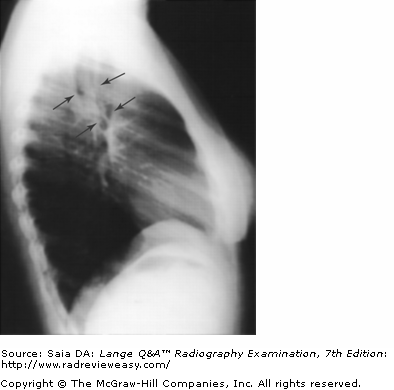

Which of the following statements is (are) true regarding the radiograph shown in Figure 6–16?

B 2 only

-The patient is well positioned; the spinous processes and sternum are seen clearly without superimposition. Adequate penetration and long-scale contrast are present without excessive receptor exposure. The patient had been shielded properly for the PA projection, but the shield was not moved to the correct location prior to the lateral exposure.